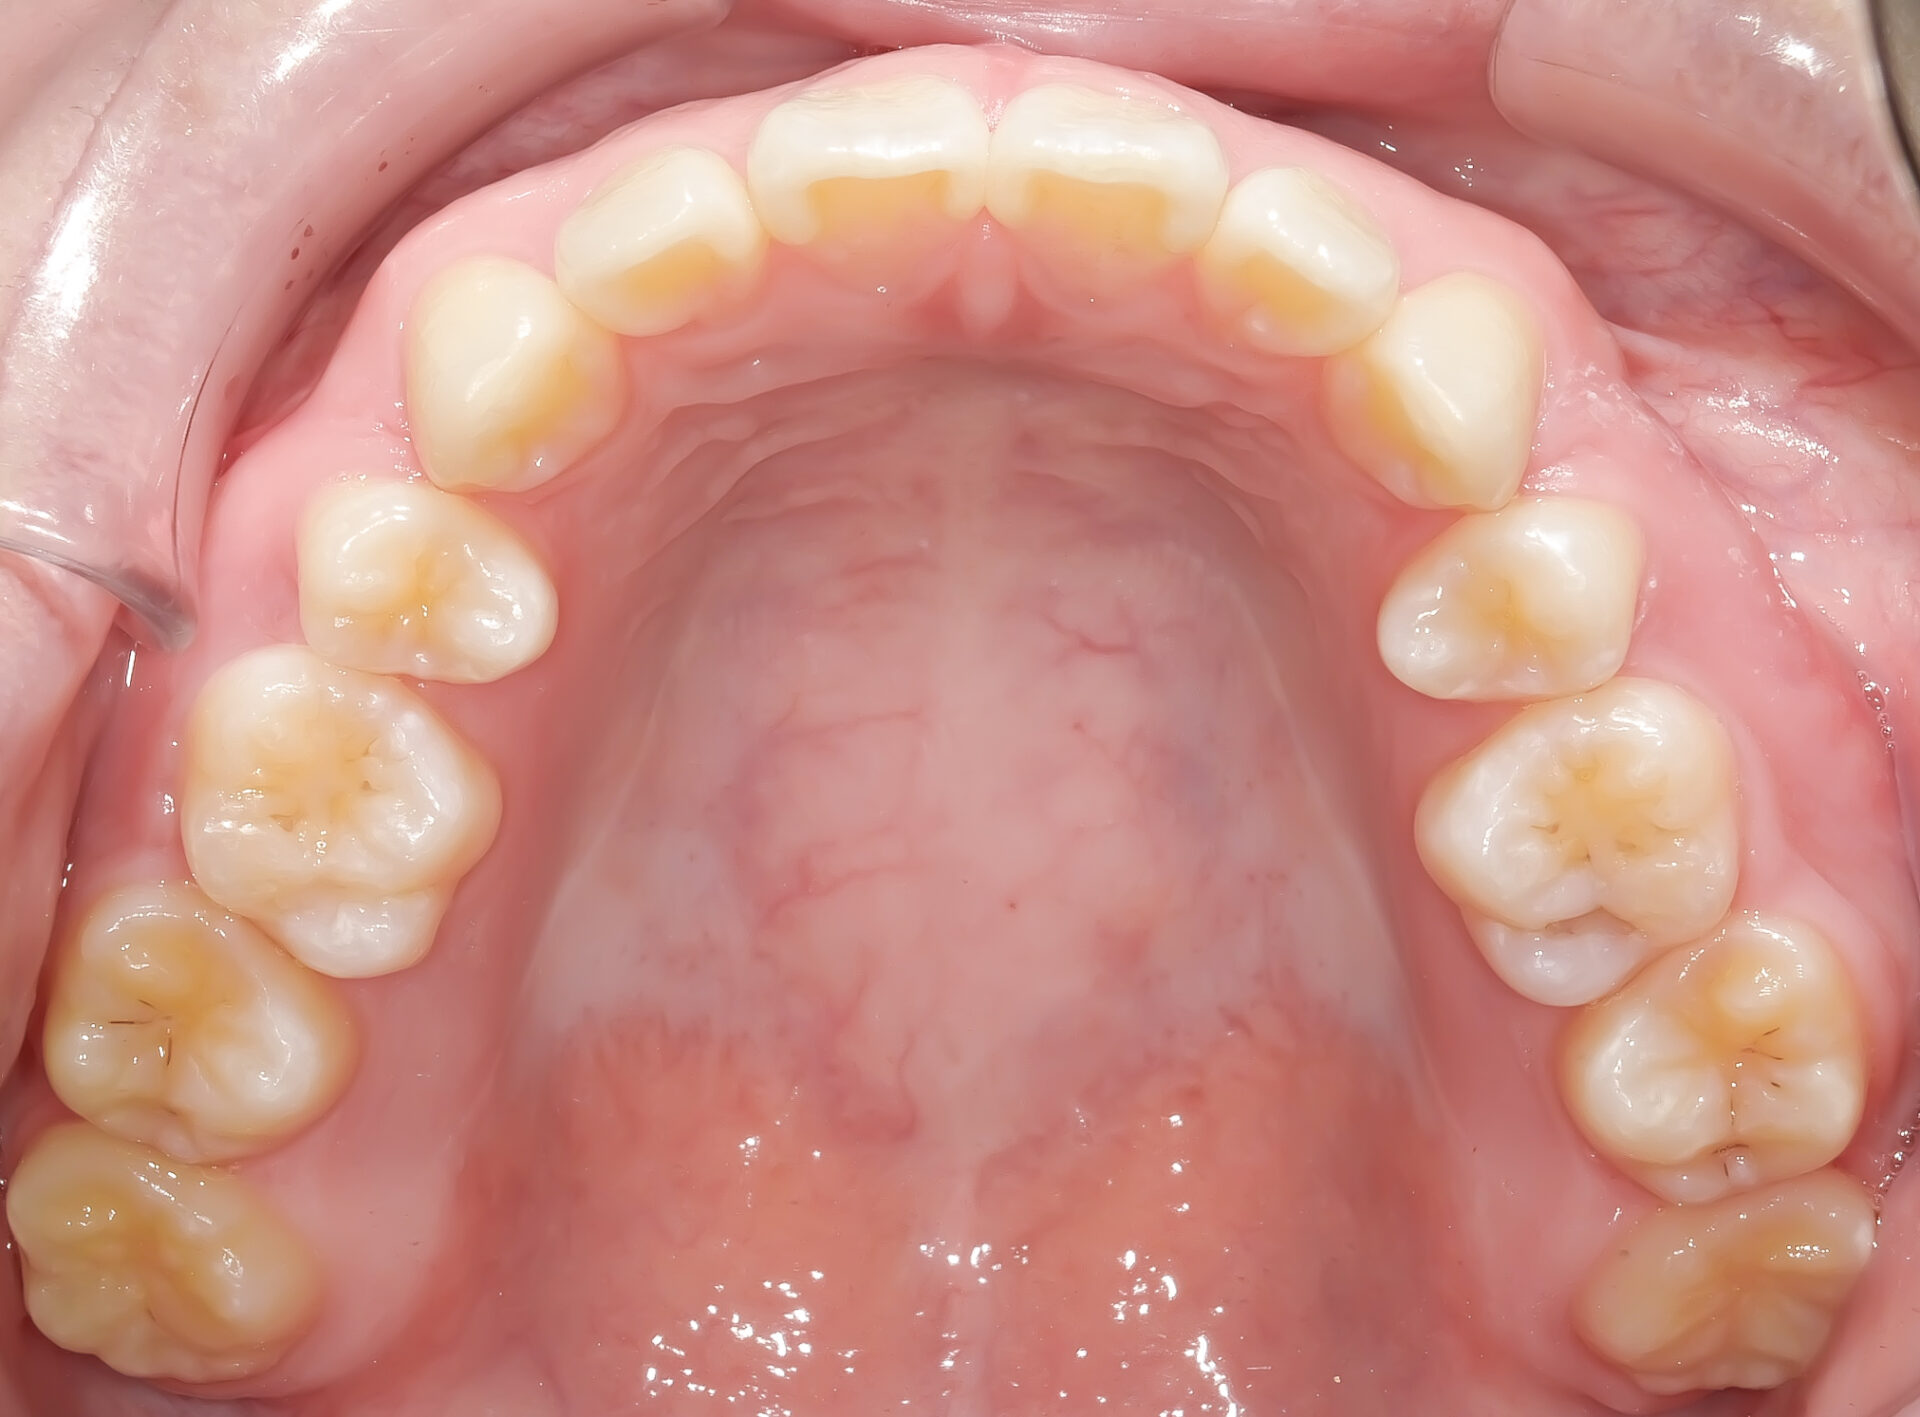

前歯2本が歯列弓(歯並びのアーチ)から外側に出ています。

ほぼすべての歯が歯列弓上にきれいに並んでいます。

上下ともしっかり並びました。